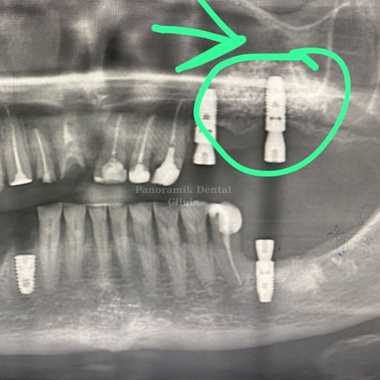

How Is Sinus Lifting Surgery Performed?

Sinus lifting is a procedure performed in the dentist’s chair under local anaesthesia. The sinus area to be removed is reached by means of a small window opened through the gingiva in that area.

After the sinus membrane covering the inside of the sinus is raised to the desired level, bone powder and grafting are applied to the created space and the area is closed with sutures. Depending on the jaw structure, the stages may progress slower or faster. This situation varies from person to person.